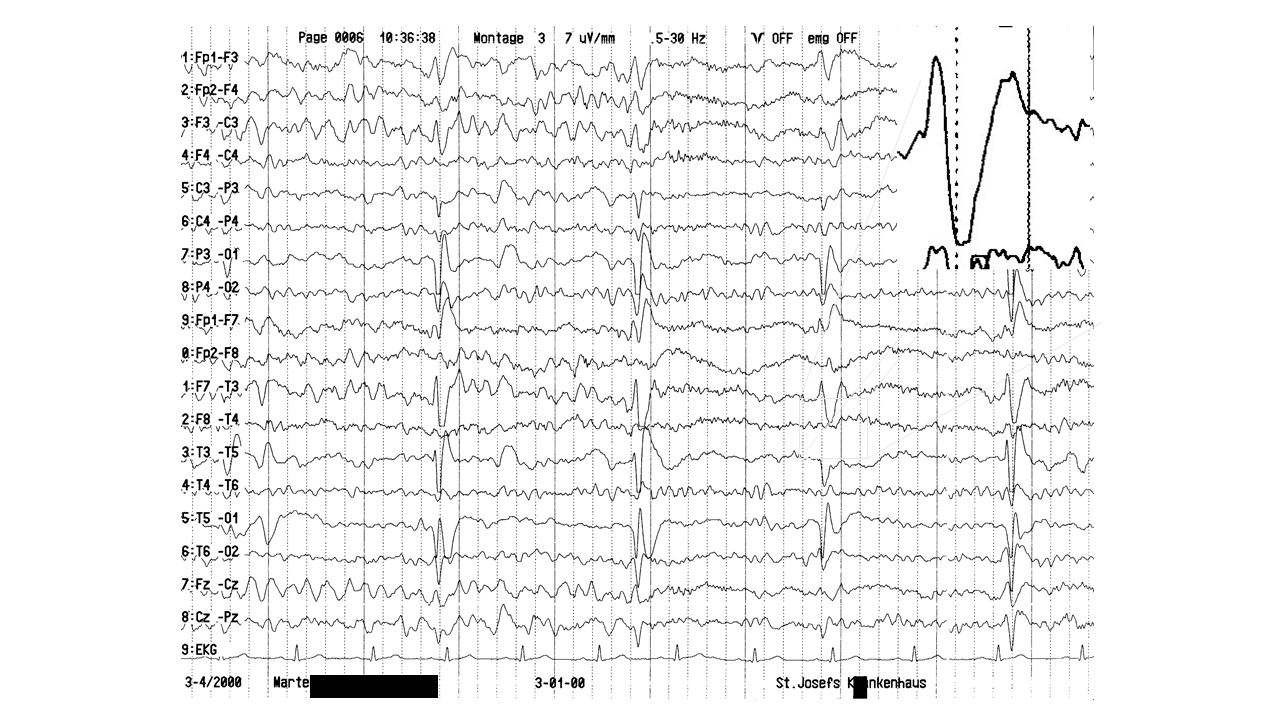

EEG-Seminar II | 13.93 zurück | weiter

folie373.jpg